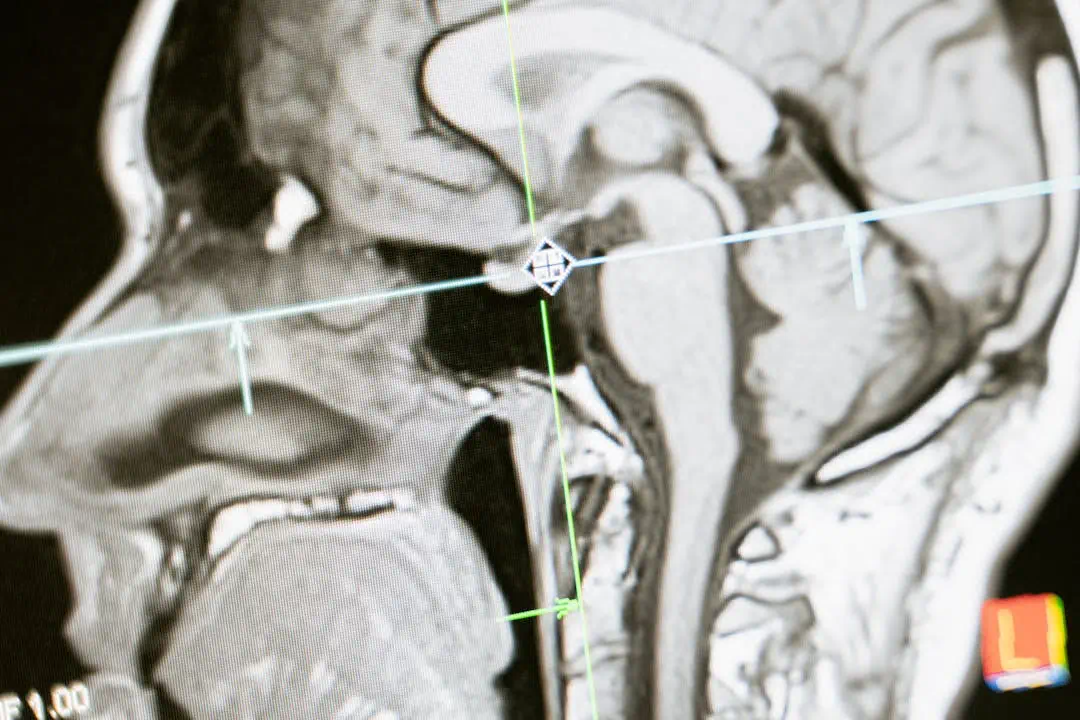

갑작스러운 신체 이상으로 병원을 찾았을 때, 의사로부터 뇌경색이라는 진단을 받는다면 당황스러움보다 먼저 치명적인 위험성을 인지해야 합니다. 뇌경색은 쉽게 말해, 뇌로 가는 혈액 공급이 차단되어 뇌 조직이 죽어가는 현상입니다.

🔵 뇌경색은 뇌졸중의 한 종류로, 전체 뇌졸중의 약 80%를 차지할 만큼 발병 비율이 매우 높습니다.

뇌세포가 산소와 영양분을 받지 못해 5분 이내 괴사 시작

❗ 뇌는 한 번 손상되면 회복이 극히 어렵기 때문에 뇌경색 초기증상을 빠르게 포착하고 대응하는 것이 무엇보다 중요합니다.